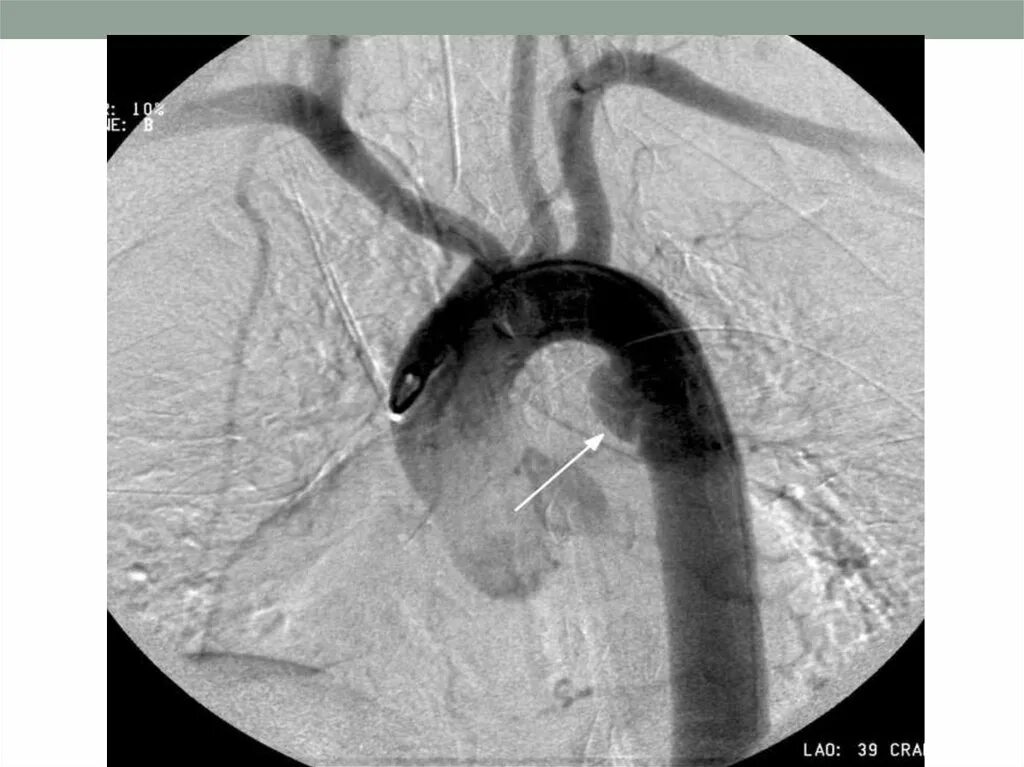

Что такое аортосклероз легких и как лечить